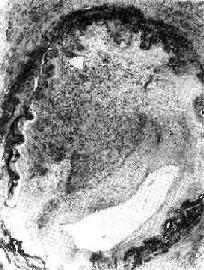

图3-6 机化的血栓 血管腔内的血栓已为肉芽组织取代有再通现象 2.栓塞 在血栓未和血管壁牢固粘着之前,血栓的整体或部分可以脱落,形成栓子,随血流运行,引起栓塞。如栓子内含着细菌,可引起栓塞组织的败血性梗死或栓塞性脓肿。 3.心瓣膜变形 心瓣膜血栓机化,可引起瓣膜粘连,造成瓣膜狭窄,如在机化过程中纤维组织增生而后瘢痕收缩,可造成瓣膜关闭不全,见于风湿性心内膜炎和亚急性细菌性心内膜炎。 4.微循环的广泛性微血栓形成,即DIC,可引起全身性广泛出血和休克。